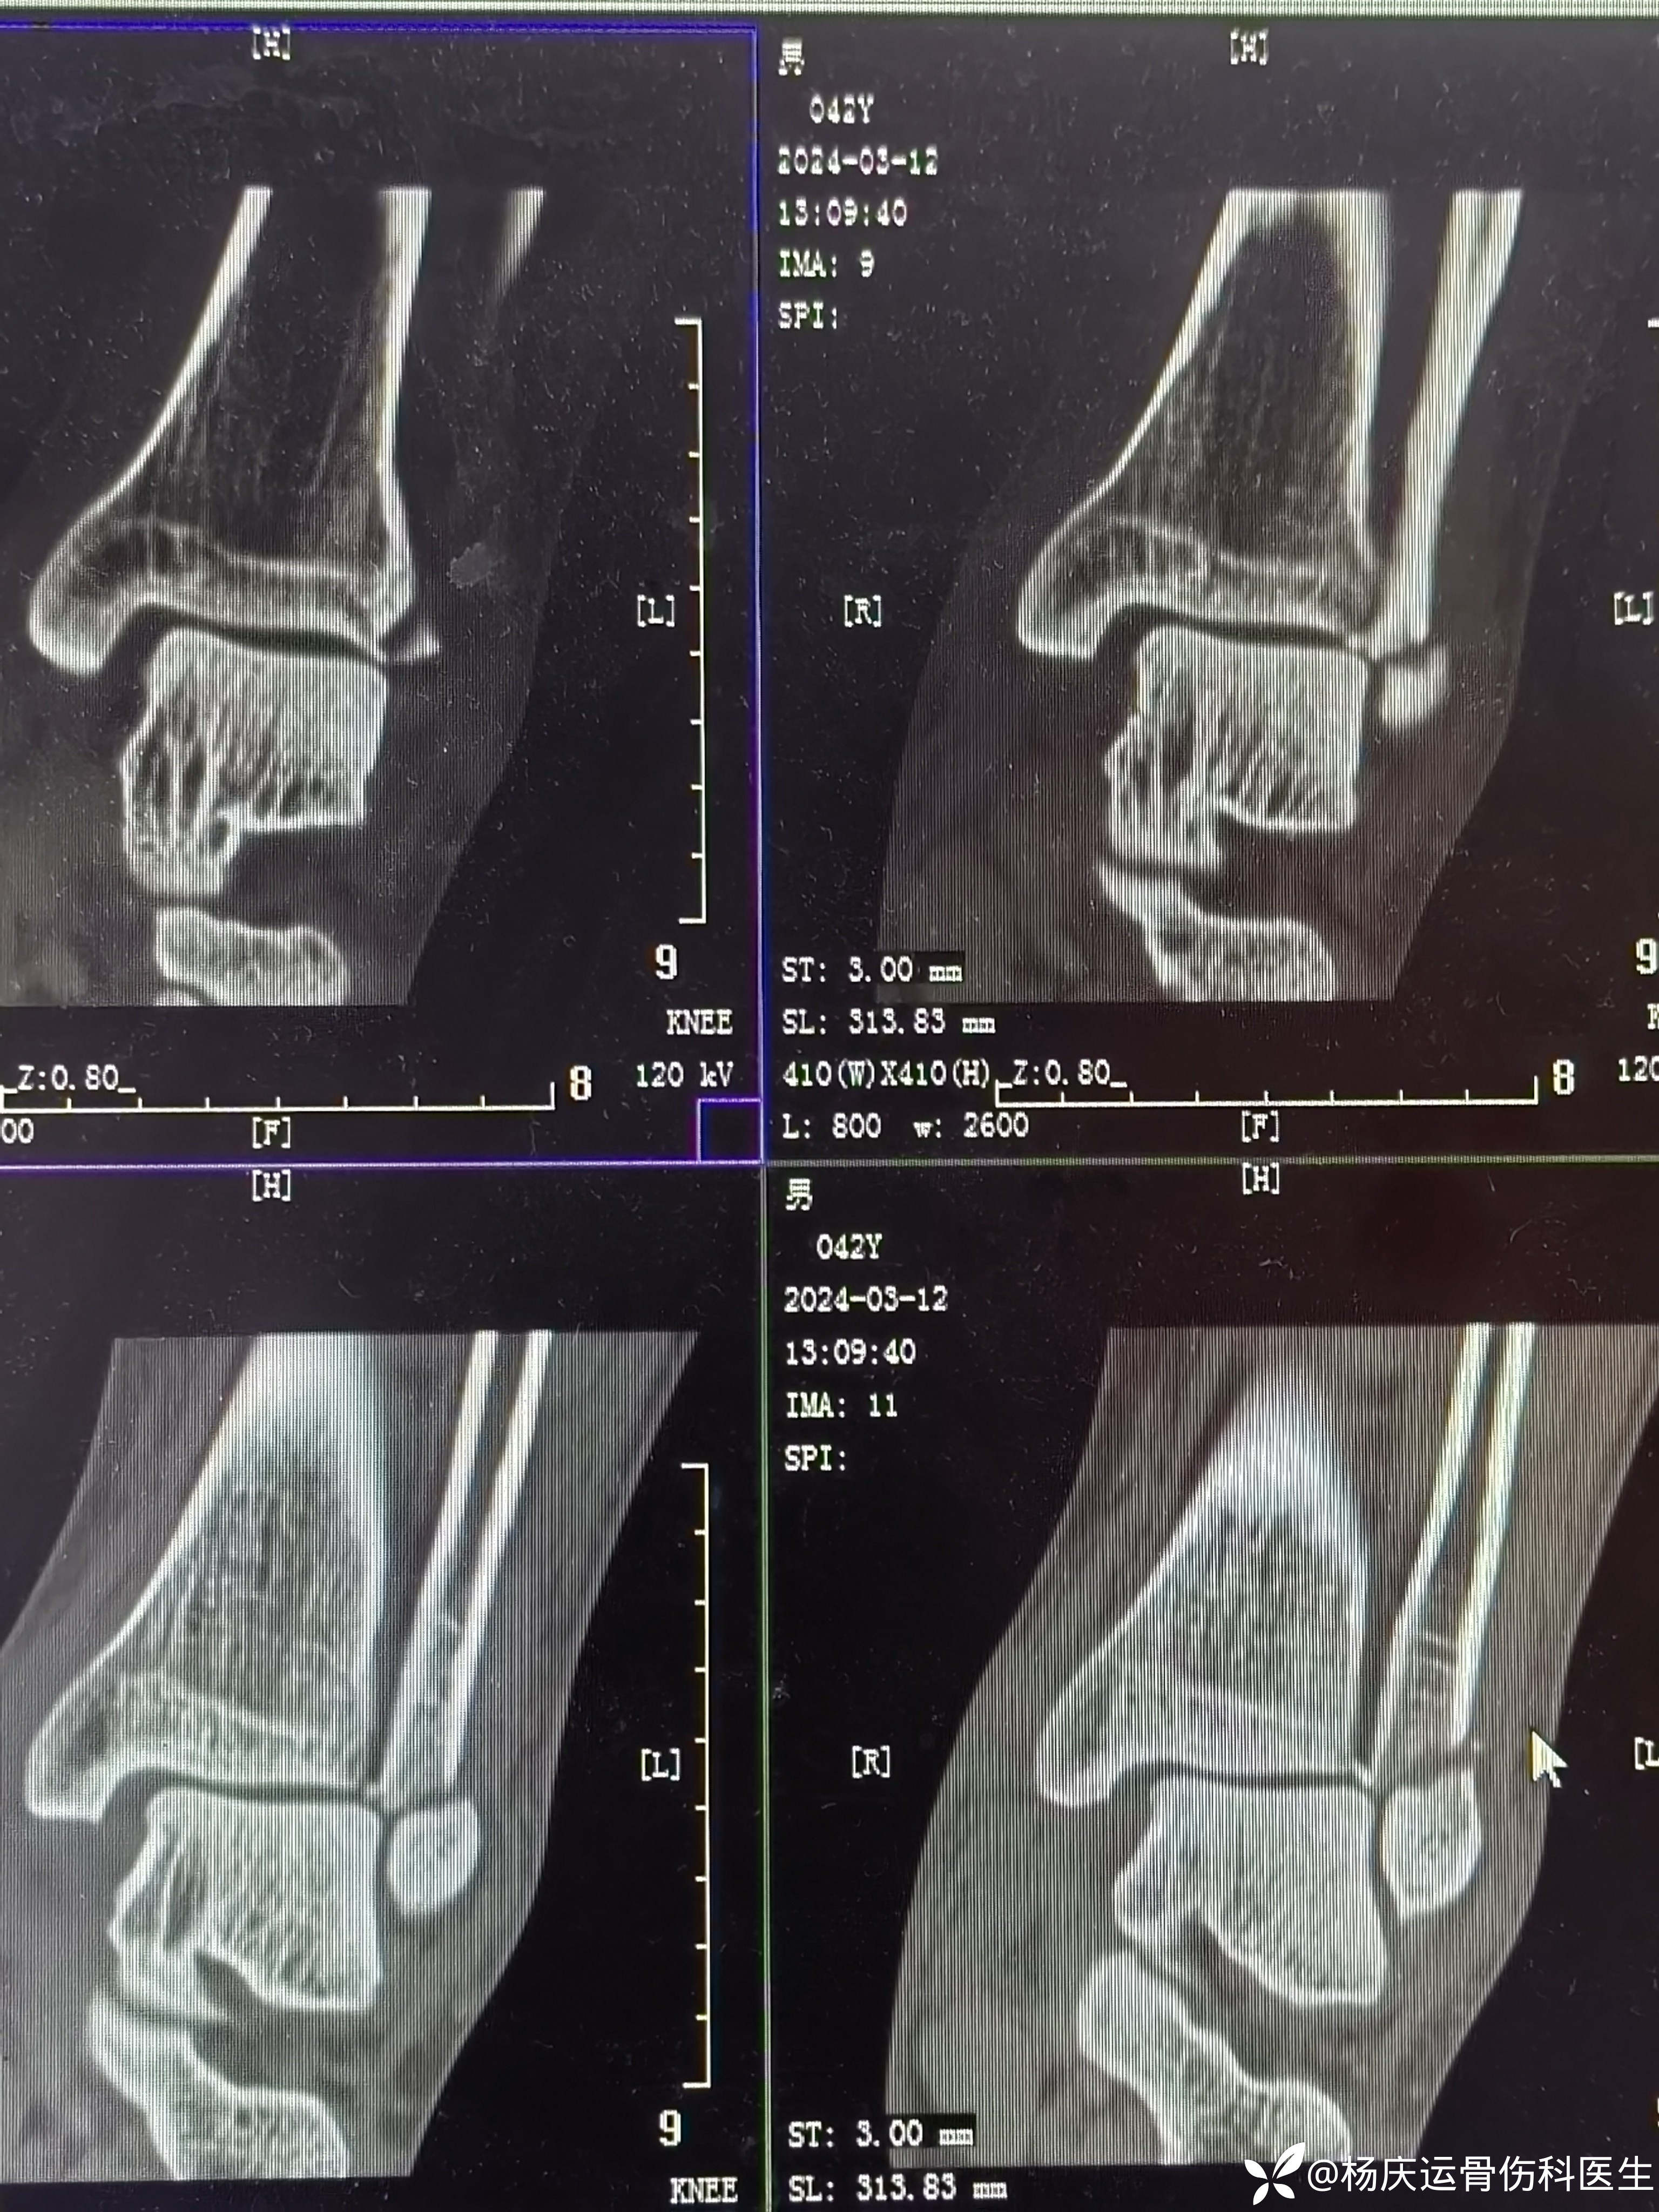

复位前CT